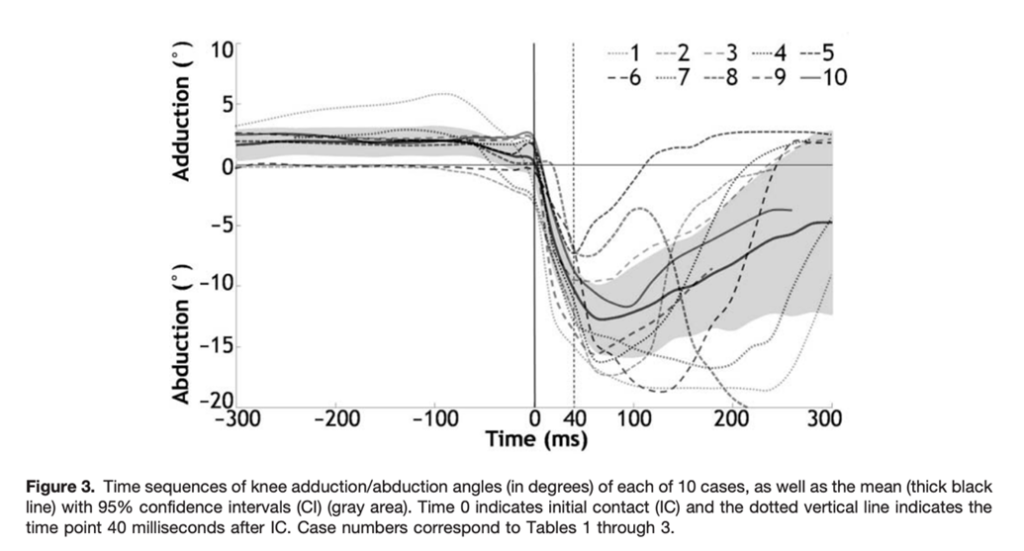

No caso de Murray, é possível identificar em vídeo a lesão com o joelho em valgo, que ocorre sem nenhum trauma direto. Em estudo retrospectivo que avaliou 1000 casos de lesões de LCA em atletas adolescentes, 67% das lesões no basquete também ocorreram sem contato direto, associadas à aterrisagem ou giro e mudança de direção (7). Este mecanismo de lesão do LCA no basquete também já foi discutido em uma série de 39 vídeos (8). Ainda com relação a biomecânica no momento da lesão, Koga et al (2010) evidenciou que após 40 milisegundos do contato inicial ao solo, ocorre um aumento da flexão (24º) e valgo (12º), acompanhados por uma rotação interna inicialmente (8º) seguida pela rotação externa (17º) com uma carga de 3,2 vezes o peso corporal (9) (Fig. 1 -3).

Fig. 1 – Reprodução da Fig. 3 de Koga H, et al. Mechanisms for noncontact anterior cruciate ligament injuries: knee joint kinematics in 10 injury situations from female team handball and basketball. Am J Sports Med. 2010

Fig. 1 – Reprodução da Fig. 3 de Koga H, et al. Mechanisms for noncontact anterior cruciate ligament injuries: knee joint kinematics in 10 injury situations from female team handball and basketball. Am J Sports Med. 2010